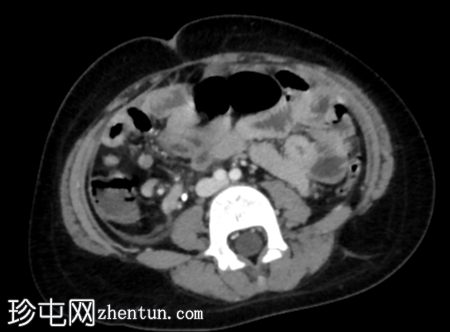

轴位增强扫描(门静脉期)

阑尾扩张,壁增厚并强化,周围阑尾周围脂肪组织条索状改变。

阑尾尖端近端可见局灶性壁缺损。

该缺损旁可见一小环状强化积液。

结肠周围及肠系膜区可见多个肿大淋巴结。

腹膜增厚。

影像

学表现符合急性阑尾穿孔的诊断,阑尾尖端近端可见局灶性壁缺损。环状强化积液提示阑尾周围脓肿。

术中发现证实了影像诊断,阑尾发炎,阑尾尖端近端有壁缺损,阑尾周围区域有脓液积聚。